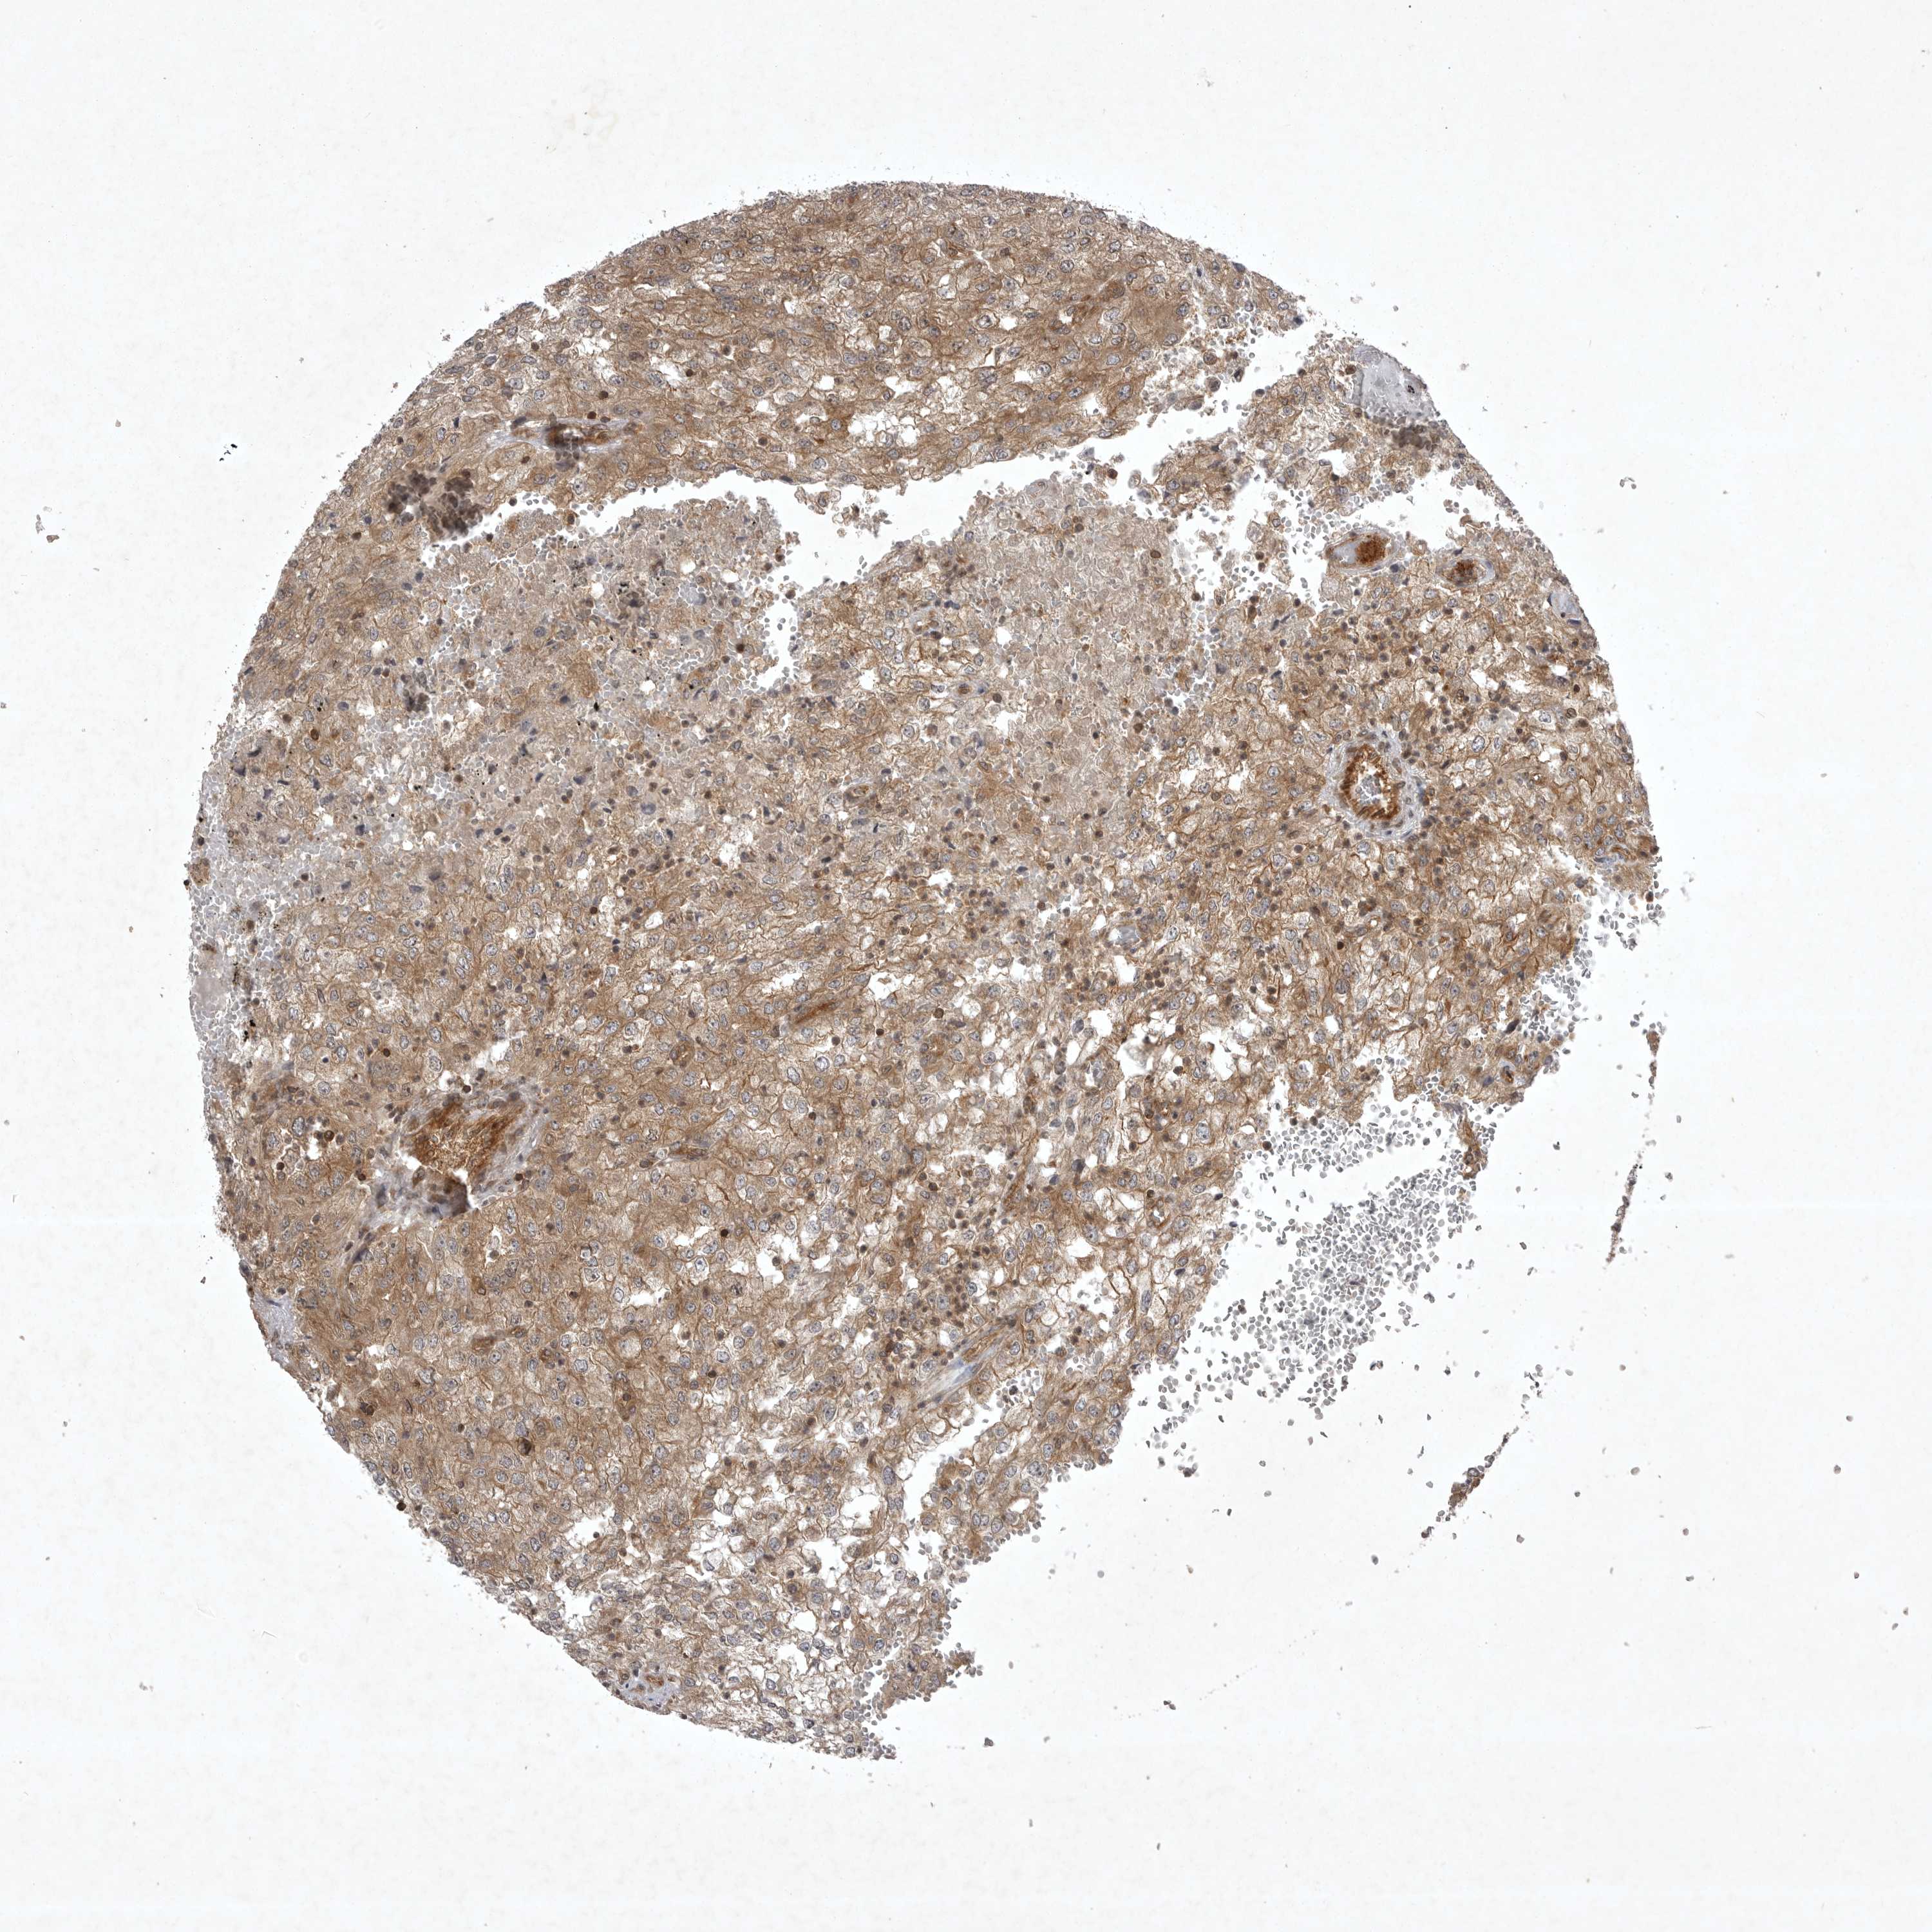

KIDNEY RENAL CLEAR CELL CARCINOMA (TCGA) - Interactive survival scatter ploti

The Survival Scatter plot shows the clinical status (i.e. dead or alive) for all individuals in the patient cohort, based on the same data that underlies the corresponding Kaplan-Meier plots. Patients that are alive at last time for follow-up are shown in blue and patients who have died during the study are shown in red.

The x-axis shows the expression levels (FPKM) of the investigated gene in the tumor tissue at the time of diagnosis. The y-axis shows the follow-up time after diagnosis (years). Both axes are complimented with kernel density curves demonstrating the data density over the axes. The top density plot shows the expression levels (FPKM) distribution among dead (red) and alive patients (blue). The right density plot shows the data density of the survived years of dead patients with high and low expression levels respectively, stratified using the cutoff indicated by the vertical dashed line through the Survival Scatter plot. This cutoff is automatically defined based on the FPKM cutoff that minimizes the p-score. The cutoff can be changed by dragging the vertical line or by entering a cutoff value in the square labeled "Current cut-off".

Under the Survival Scatter plot the p-score landscape (black curve; left axis) is shown together with dead median separation (red curve; right axis). Dead median separation is the difference in median mRNA expression between patients who have died with high and low expression, respectively. It is calculated as follows: median FPKM expression of dead patients with high expression - median FPKM expression of dead patients with low expression. This is intended to aid the user in visually exploring custom cutoffs and the associated p-scores and dead median separation.

Individual patient data is displayed and can be filtered by clicking on one or more of the category buttons on the top of the page. Categories describing expression level and patient information include: high, low, alive, dead, female, male and tumor stages. The scale of the x-axis can be toggled between linear and log-scale by clicking on the "x log" button. Mouse-over function shows TCGA ID, patient information and mRNA expression (FPKM) for each patient.

& Survival analysisi

Kaplan-Meier plots summarize results from analysis of correlation between mRNA expression level and patient survival. Patients were divided based on level of expression into one of the two groups "low" (under cut off) or "high" (over cut off). X-axis shows time for survival (years) and y-axis shows the probability of survival, where 1.0 corresponds to 100 percent.

STK24 is validated prognostic, high expression is favorable in Kidney Renal Clear Cell Carcinoma (TCGA)

Best expression cut offi

Based on the FPKM value of each gene, patients were classified into two groups and association between prognosis (survival) and gene expression (FPKM) was examined. The best expression cut-off refers the FPKM value that yields maximal difference with regard to survival between the two groups at the lowest log-rank P-value. Best expression cut-off was selected based on survival analysis .

When clicking on this number, the vertical dashed line indicating cut-off, the interactive survival plot, and the Kaplan-Meier curve will be adjusted to show results based on the best expression cut-off.

: 58.14

Average pTPM 66.4

Number of samples 521